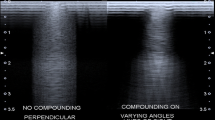

The US image is processed to optimize the appearance on the display. All echo signals are uniformly preamplified after detection by the transducer, and uniform user-controllable gain is applied. Equally reflective structures are displayed in the B-mode image with the same brightness, regardless of their depth. The dynamic range of the echo signals is also compressed to reduce the gain for larger signal magnitudes and increase the gain for smaller signal magnitudes. These signals are also demodulated to remove oscillations at the ultrasound frequency, and very small signals are removed in order to reduce image noise and clutter. Other steps are designed to obtain sharper edges and improved contrast. Among recent innovations in B-mode US, a mode called spatial compound imaging is a new approach to smooth the speckle in order to make the images look less grainy. Spatial compound images smooth the speckle, noise, clutter, and refractive shadows and improve contrast and margin definition [8].